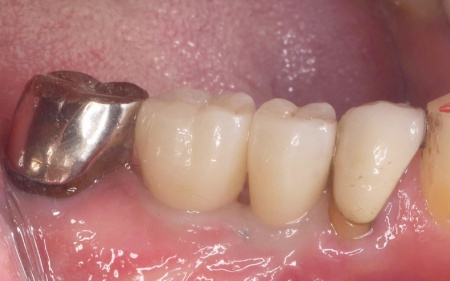

60代男性 根が割れた歯を抜歯してインプラント治療を施した症例

定期健診で通院されていた患者様より「右下の歯ぐきが腫れてきた」とご相談いただきました。

拝見したところ、右下の奥歯周辺の歯ぐきが腫れていました。

歯やあごの骨の状態を詳しく調べるためレントゲン検査を行った結果、右下の奥歯2本(第2小臼歯、第1大臼歯)は、歯根が縦方向に割れている可能性が高いと考えられました。

そこで歯ぐきの一部を開き内部を直接確認したところ、いずれの歯根が垂直方向に割れていました。

歯根が割れている場合、細菌感染が進行して歯ぐきの炎症が広がったり周囲の歯やあごの骨にまで影響を及ぼしたりする可能性があります。

以上のことから、歯を温存することは難しいため抜歯が必要と診断しました。

歯ぐきの治癒を待ってから型取りを行い、インプラントの上に装着する人工歯を作製・装着して治療を終了しています。